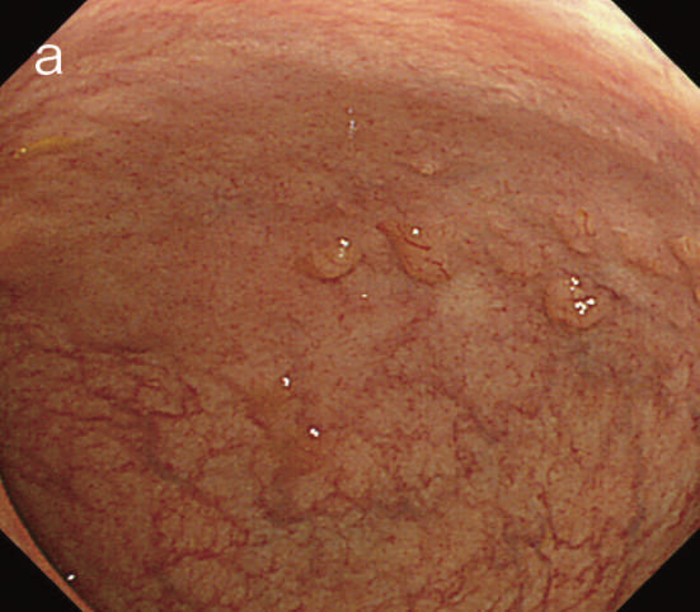

- 白色光像:直腸(直腸S状部)の発赤調変化。背景粘膜は寛解期にあった。

- 色素内視鏡像:病変辺縁が明瞭となるが,病変肛門側で不明瞭であった。